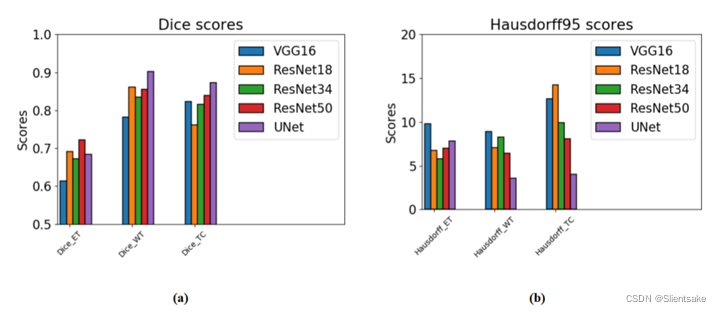

评估不同编码器主干的有效性。为此,作者在带有完整CC+GC和5迭代CGA-CRF的BraTS2017训练集上使用了5倍交叉验证。作者在这里选择最先进的编码器主干,例如VGG16、ResNet18、ResNet30、ResNet50和UNet编码器路径。对于每个主干,将来自最后一个卷积块的特征图馈送到特征交互图分支,以提取交互图上下文并将来自第二个最后卷积块的特征图馈送到卷积分支,以生成深度监督特征图。实践证明,这种做法有效、高效、简单。关于Dice和Hausdorff95的分割结果如图8所示。ResNet优于VGG16,主要是因为涉及到剩余连接和批量标准化。然而,与ResNet和UNet的编码器相比,UNet的编码器由于多尺度特征映射和跳过连接进行特征融合,在Dice和Hausdorff95方面获得了更好的分割性能。在作者的方法中,选择UNet的编码器作为最终分割模型的主干网络。

图8。不同编码器主干的性能比较:(a)和(b)分别通过使用不同编码器主干对BraTS2017训练集进行交叉验证,表明与dice分数和Hausdorf95的比较。